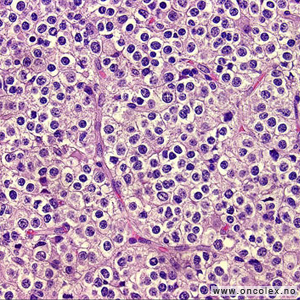

Primære SNS-lymfomer

Primære ondartede lymfomer i sentralnervesystemet er sjeldne og er en betegnelse på lymfekreft som har oppstått i sentralnervesystemet. Disse svulstene hyppigere hos pasienter med redusert immunforsvar, blant annet hos AIDS-pasienter og hos pasienter som har blitt transplanterte. Cellegift, og i noen tilfeller strålebehandling, er de mest aktuelle behandlingsformene for å søke å få kontroll på sykdommen. Operasjon brukes bare for å få bekreftet diagnosen.